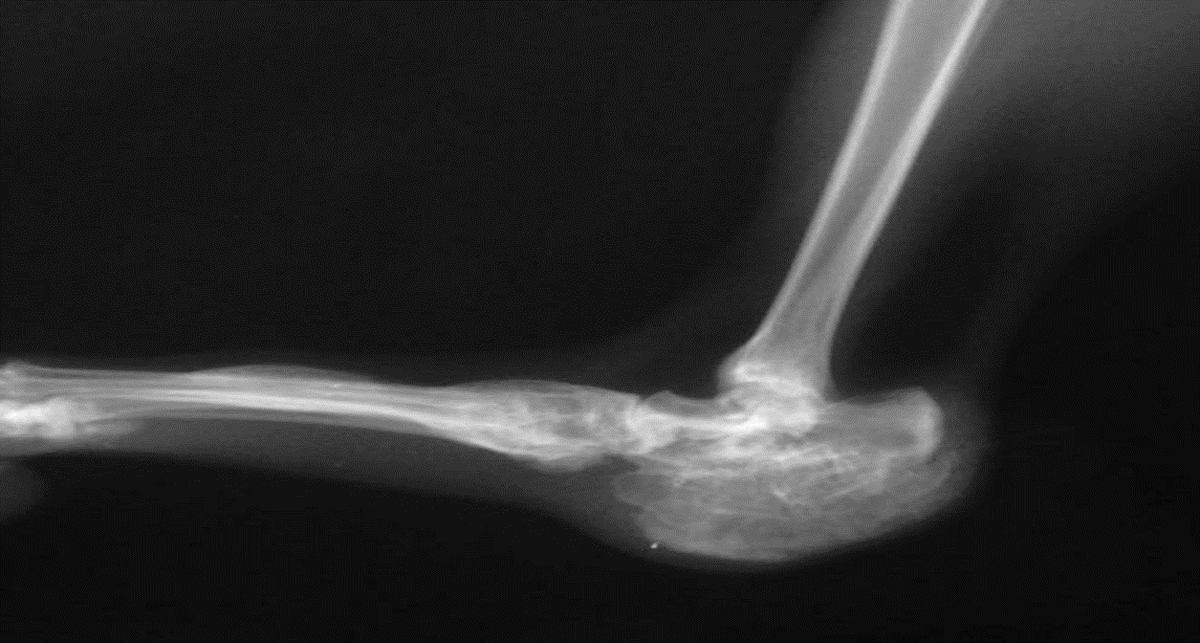

И легко догадаться, что если Са в кости будет мало, то кость станет не прочной, размягченной, наступит такое состояние, как остеопороз, которое неизбежно закончится переломами. Поэтому существует расхожее мнение, что Са – это для кости. А так ли это?

-4